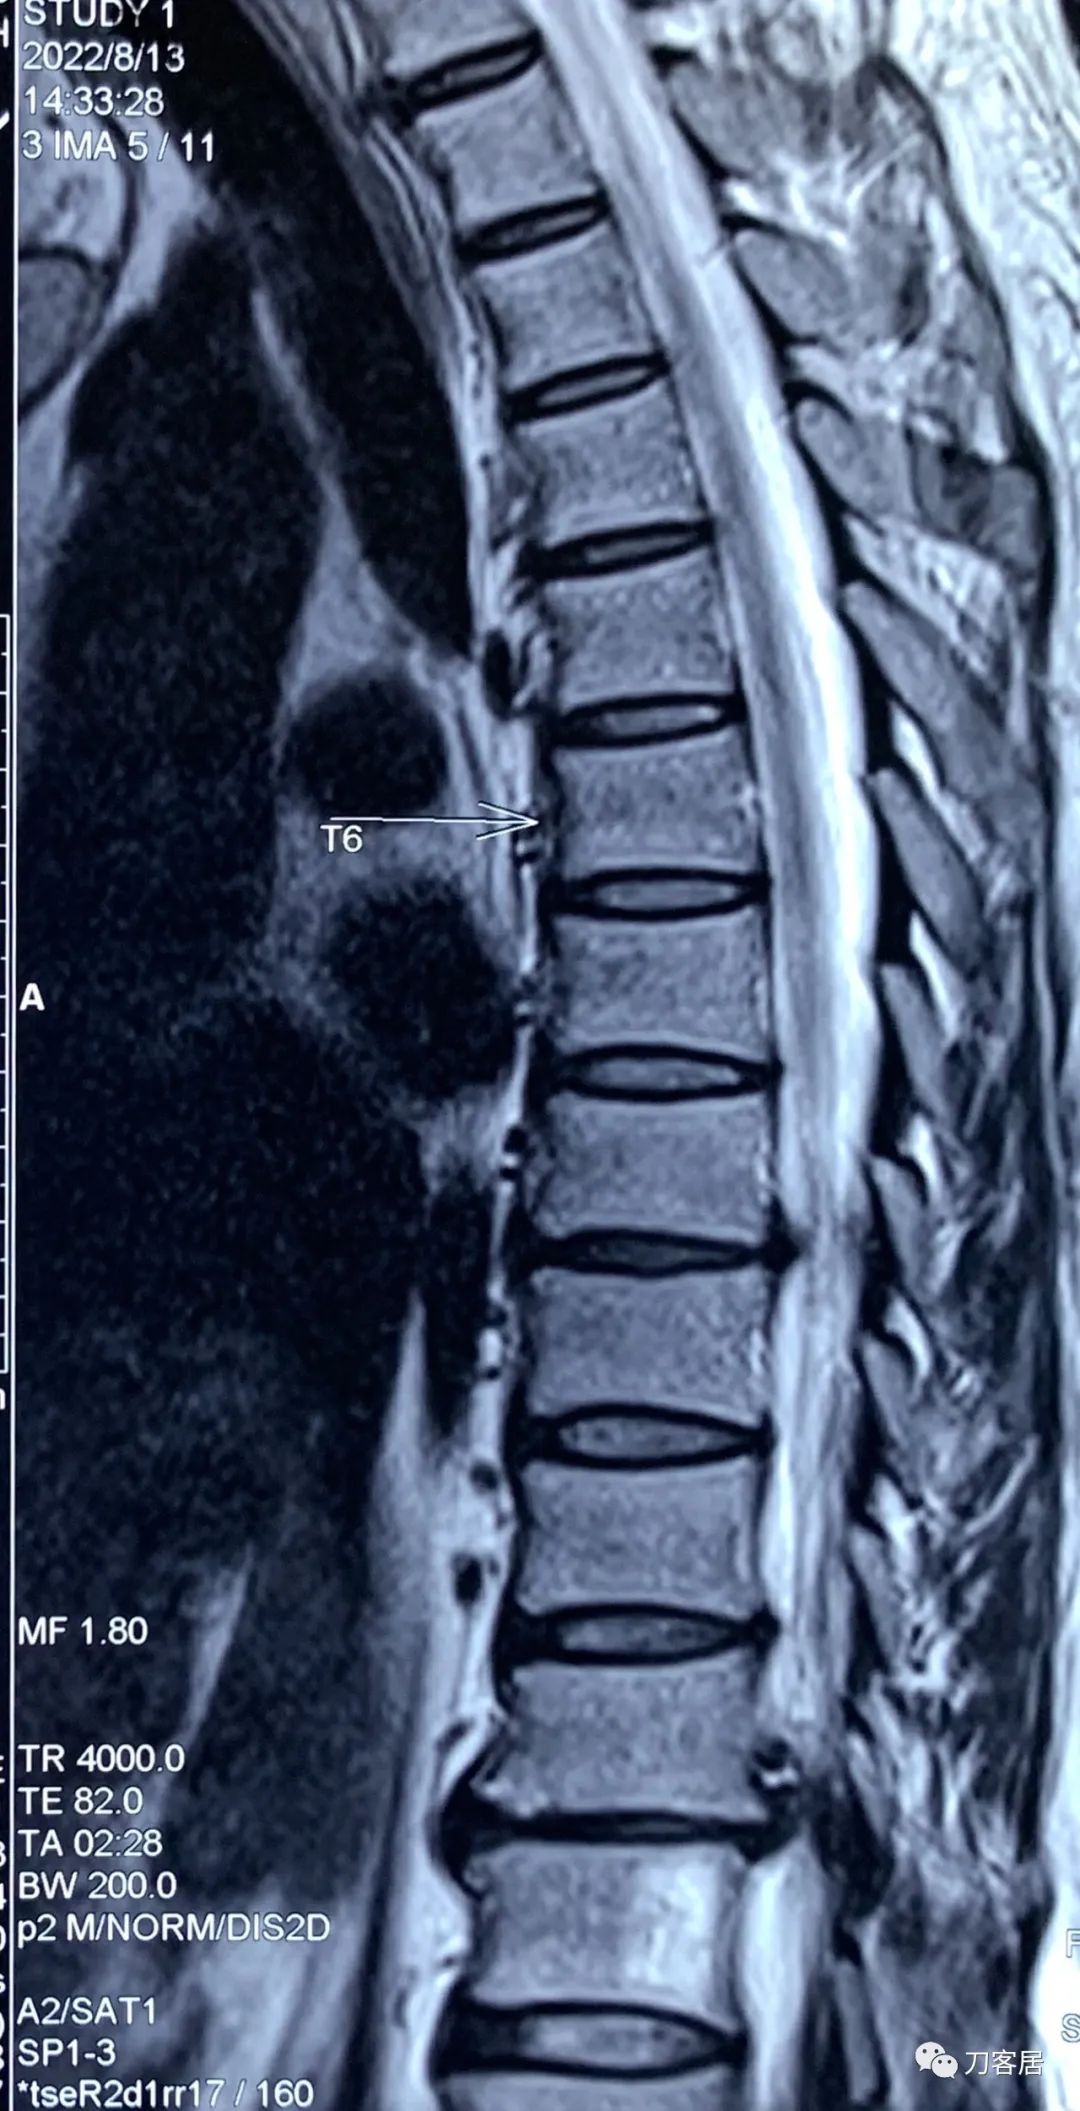

图7. 20220813西安第三方影像机构胸椎MRI01,提示胸8-9椎间盘突出,胸11-12椎间盘突出,椎管狭窄。

图8. 20220813西安第三方影像机构胸椎MRI02,提示胸8-9椎间盘突出,胸11-12椎间盘突出,椎管狭窄。